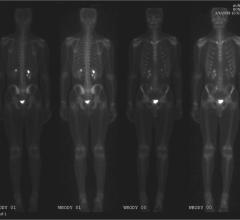

UltraSPECT Inc. announced the 10th anniversary of the U.S. Food and Drug Administration (FDA) approval of its Wide Beam Reconstruction (WBR) technology.